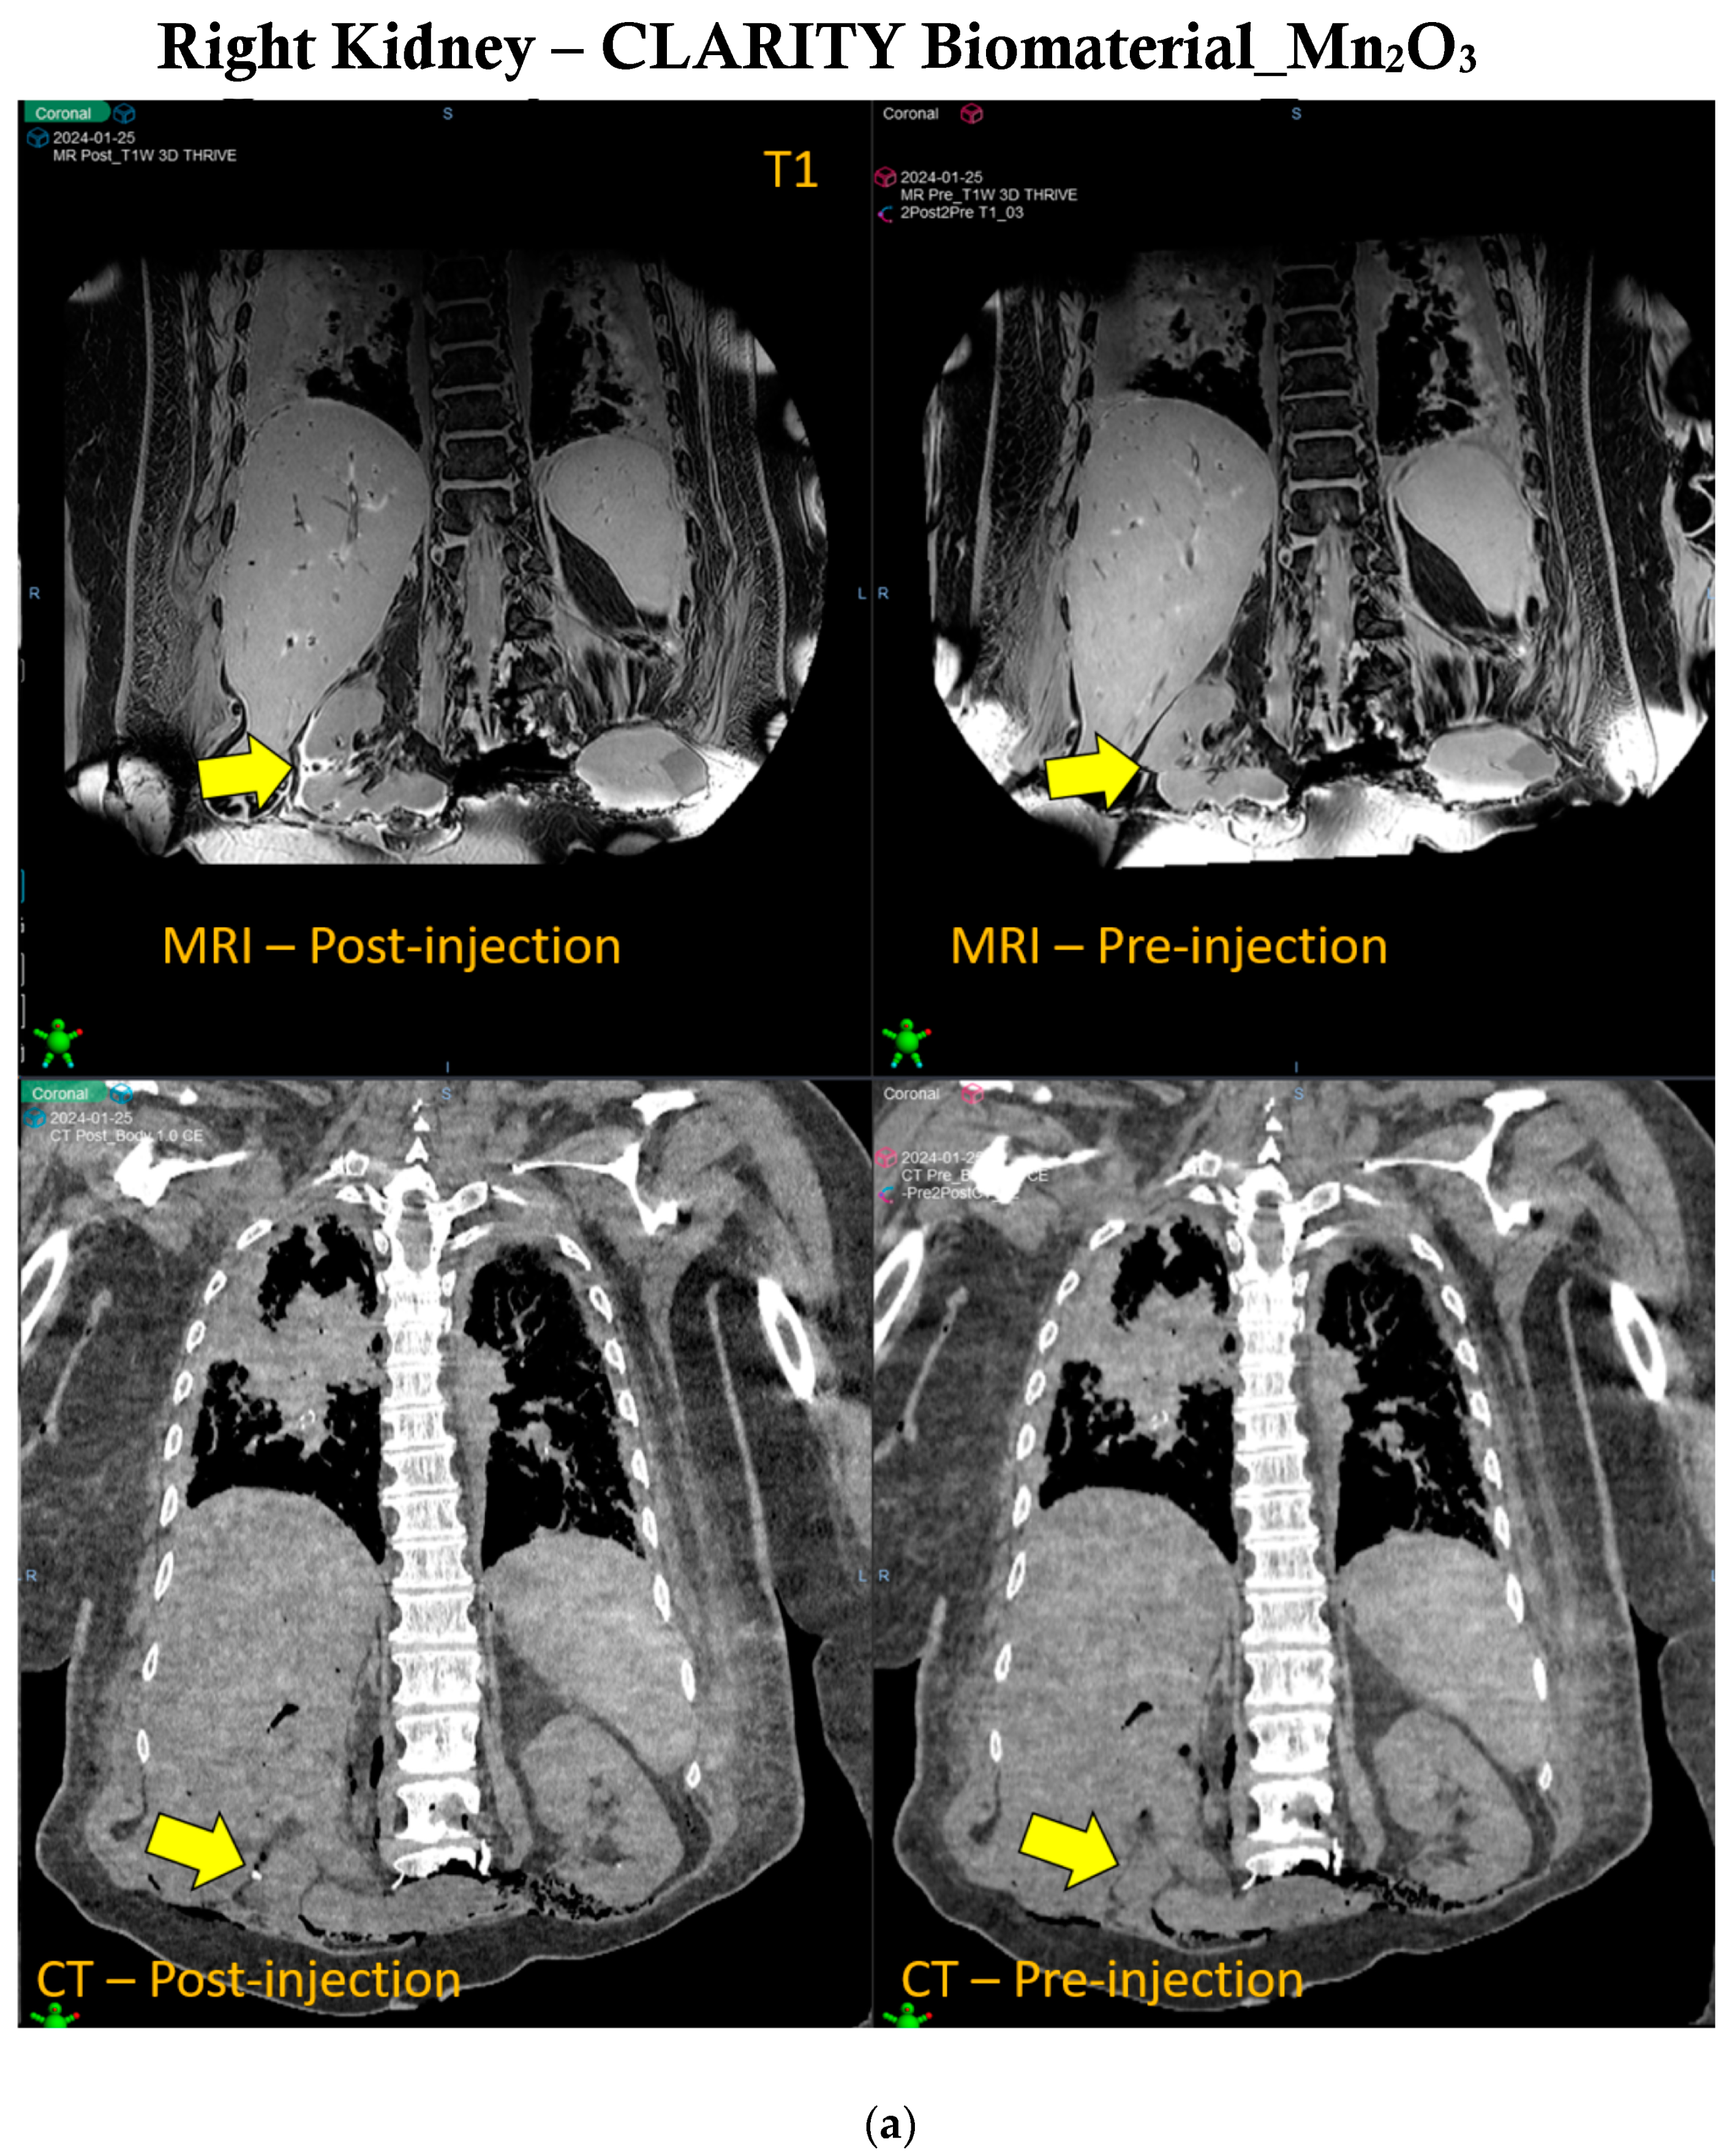

3.2. Image Guidance of CLARITY Biomaterial in Pancreatic Cancer